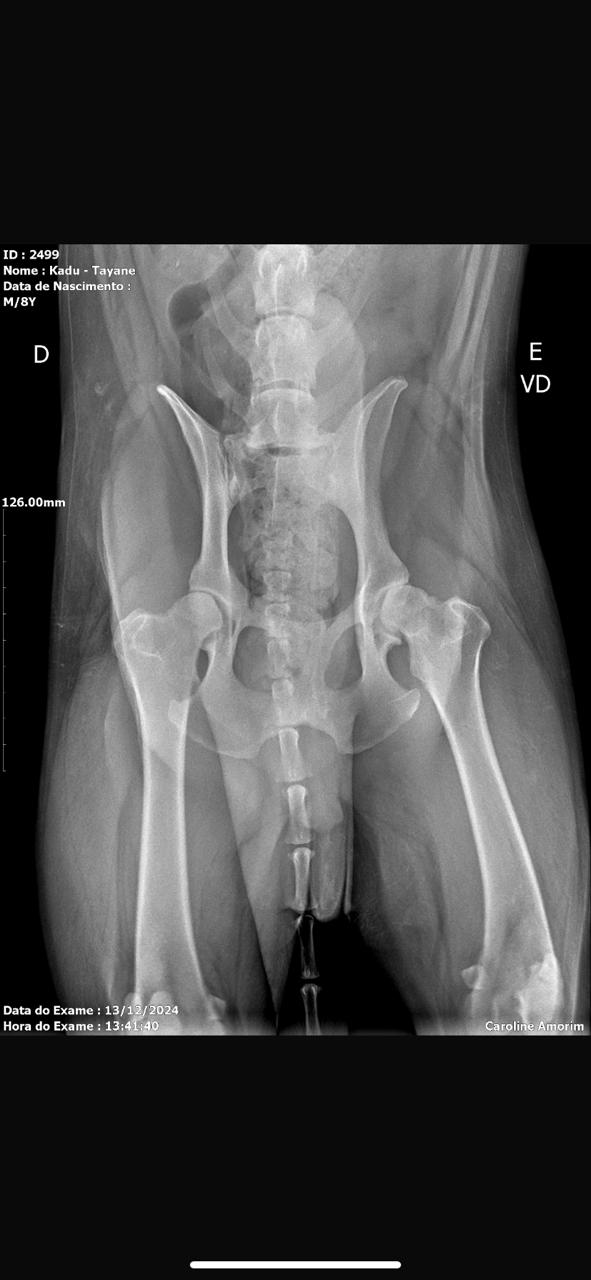

Displasia coxofemoral, que é uma doença que afeta a articulação do quadril do animal, causando dificuldade de se movimentar (andar, saltar, levantar) e degeneração articular.